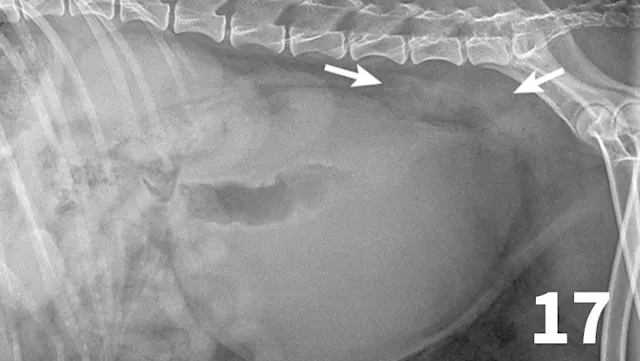

Survey radiographs of the urinary bladder are helpful for evaluation of size and location and for detection of radiopaque calculi. Urinary bladder distention is readily detected (Figure 17). Radiographs are of limited value in evaluating mural disease because the bladder wall cannot be differentiated from the fluid contained within the bladder. Bladder wall thickening (eg, bacterial inflammation, polypoid cystitis, neoplasia) is best evaluated by ultrasonography or double-contrast cystography (Figure 18). It should be noted that the degree of bladder filling can affect bladder wall thickness. For example, a small, mildly distended bladder may appear to have a thickened bladder wall on ultrasound compared with a moderately or severely distended bladder (Figure 19). This potential disadvantage can often be overcome by reevaluating the bladder several hours after preventing voiding.

Figure 17.

This dog had a severely distended urinary bladder on evaluation of lateral abdominal radiographs. Ill-defined, soft tissue opacity was present in the region of the medial iliac lymph nodes (arrows). The dog had urethral neoplasia, which was the cause of the urinary outflow obstruction and lymph node enlargement.